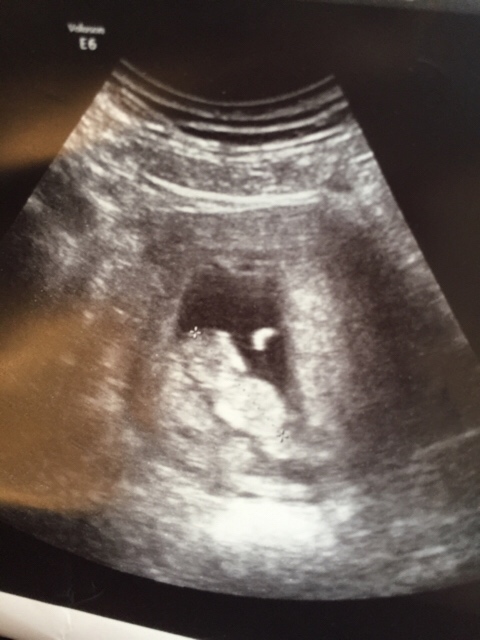

Gråter!!!!! Masse blod på papiret og redd for det har gått galt!!! Skal til privat ul klokken 12:00. Orker ikke styre med legevakta. For de ville ikke ta ul på meg. Kun blodprøve idag og om to dager! Duster!!!!

lille babyen i magen er jeg redd er død